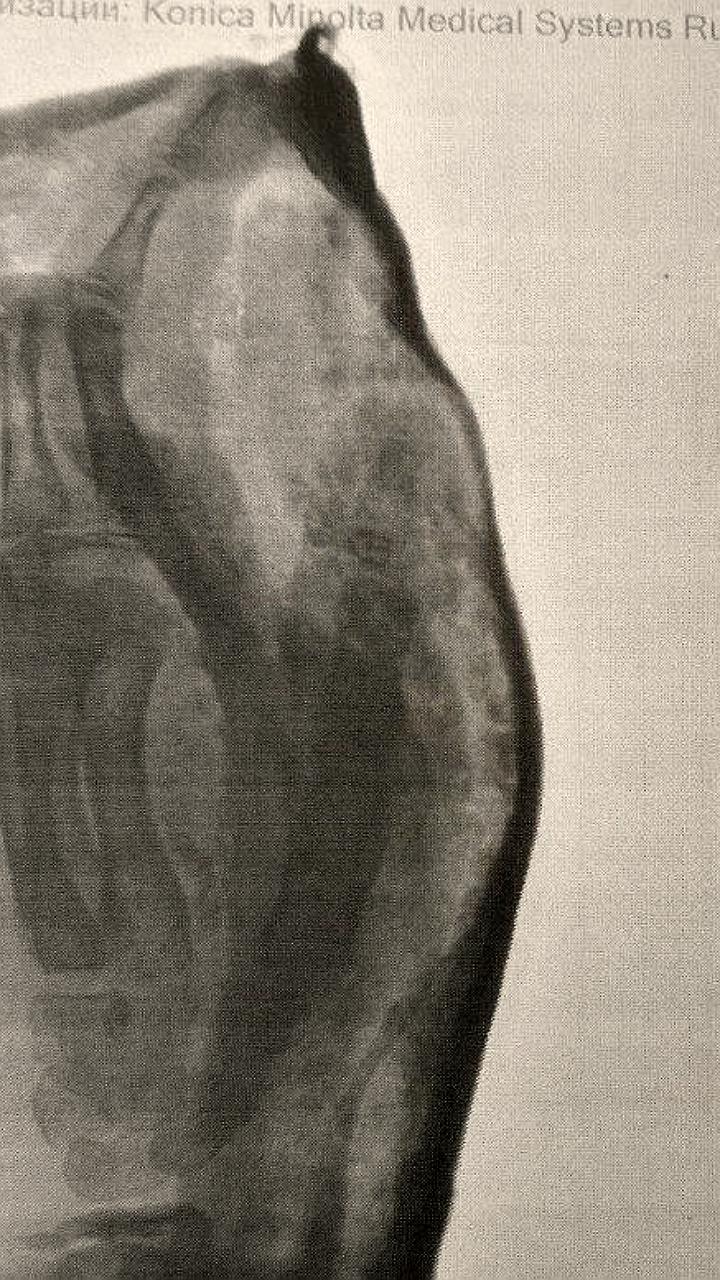

‼ В Новой Каховке в результате сброса с дрона ВСУ пострадал местный житель "Мужчина 2002 года рождения получил множественные осколочные ранения нижних конечностей и травматический отрыв 4,5 пальцев правой стопы", - сообщили в окружной администрации. Также отмечается, что пострадавший госпитализирован в Каховскую ЦРБ. Радио Таврия - подписаться

В результате сброса с дрона ВСУ в Новой Каховке пострадал мирный житель "Мужчина 2002 года рождения в результате вражеской атаки получил множественные осколочные ранения нижних конечностей и травматический отрыв 4,5 пальцев правой стопы", — сообщили в администрации Новокаховского округа. Пострадавшего госпитализировали в Каховскую центральную районную больницу. ПОДПИСАТЬСЯ НА ТАВРИЮ

Киевский режим продолжает атаковывать мирных граждан В результате сброса с дрона ВСУ около жилого дома пострадал мужчина 2002 г.р. В результате МВТ получены множественные слепые осколочные ранение нижних конечностей, травматический отрыв 4,5 пальца правой стопы. Госпитализирован в Каховскую ЦРБ.